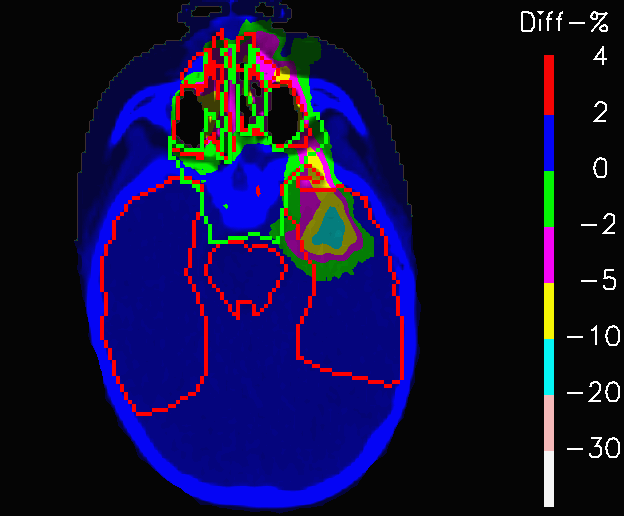

Fig.12 shows the dose distribution of PLAN-NOM and PLAN-OL, that were computed on the original CT. The plans result to be identical up to differences of 0.2%, as far as concerns both the target coverage and the sparing of the OARs.

When PLAN-NOM and PLAN-OL are re-computed on the extreme scenario CTs of Fig.4 and the difference between each of these extreme-case plan and the corresponding reference ones are considered, interesting results emerge. Fig.12 shows PLAN-NOM-H and PLAN-OL-H, whereas tables 3 highlights the fact that in both scenarios the target coverage is more remarkably more robust for PLAN-OL than for PLAN-NOM, since 𝐕𝟏𝟎𝟎subscript𝐕100\mathbf{V_{100}} improves by 3.1% in the high-density nose cavities case and by +5.3% in the other one.

Refer to caption

(a) PLAN-NOM-H

(b) PLAN-OL-H

Figure 13: Fields crossing the nasal cavities: difference between the dose distribution re-calculated on the CT with nasal cavities filled with mucus and the one computed on the original CT, for the nominal plan and the one re-computed with OL penalization.